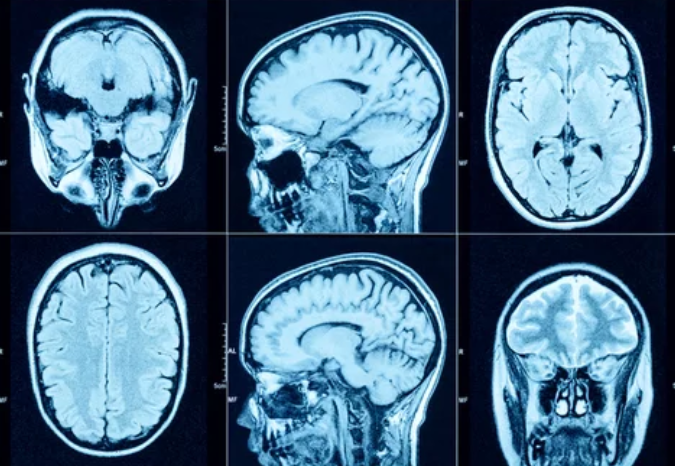

MRI uses a combination of strong magnetic fields, radiofrequency (RF) pulses, and advanced computer processing to generate detailed images of the body’s internal structures. Unlike X-rays or CT scans, MRI does not rely on ionizing radiation.

These signals are converted into high-resolution images of soft tissues, organs, and blood vessels.